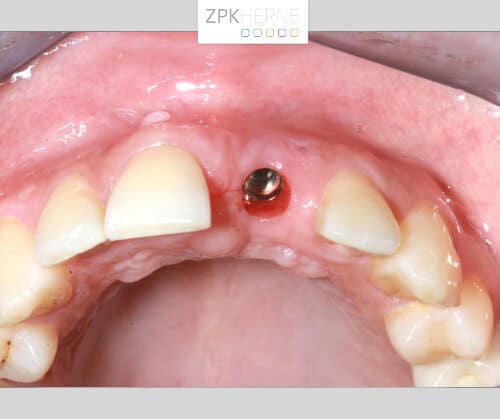

Kieferansicht mit ausgefallener Krone - Zahn 21

Zahn 21 ist austherapiert

Zunächst stellen wir den Ist-Zustand mittels Digitaler Volumentomographie (DVT) fest:

• Die vorangegangenen Therapien wie Wurzelkanalbehandlung und Stiftaufbau haben den Zahn stark in Mitleidenschaft gezogen. Außerdem ist die Wurzelspitze des Zahnes entzündet. Somit kann Zahn 21 nicht erneut versorgt, sondern muss gezogen werden: Er ist lange austherapiert.

• Positiv zu bemerken ist, dass der Wurzelrest das Knochenniveau erhält und kein extra Knochenaufbau stattfinden muss.